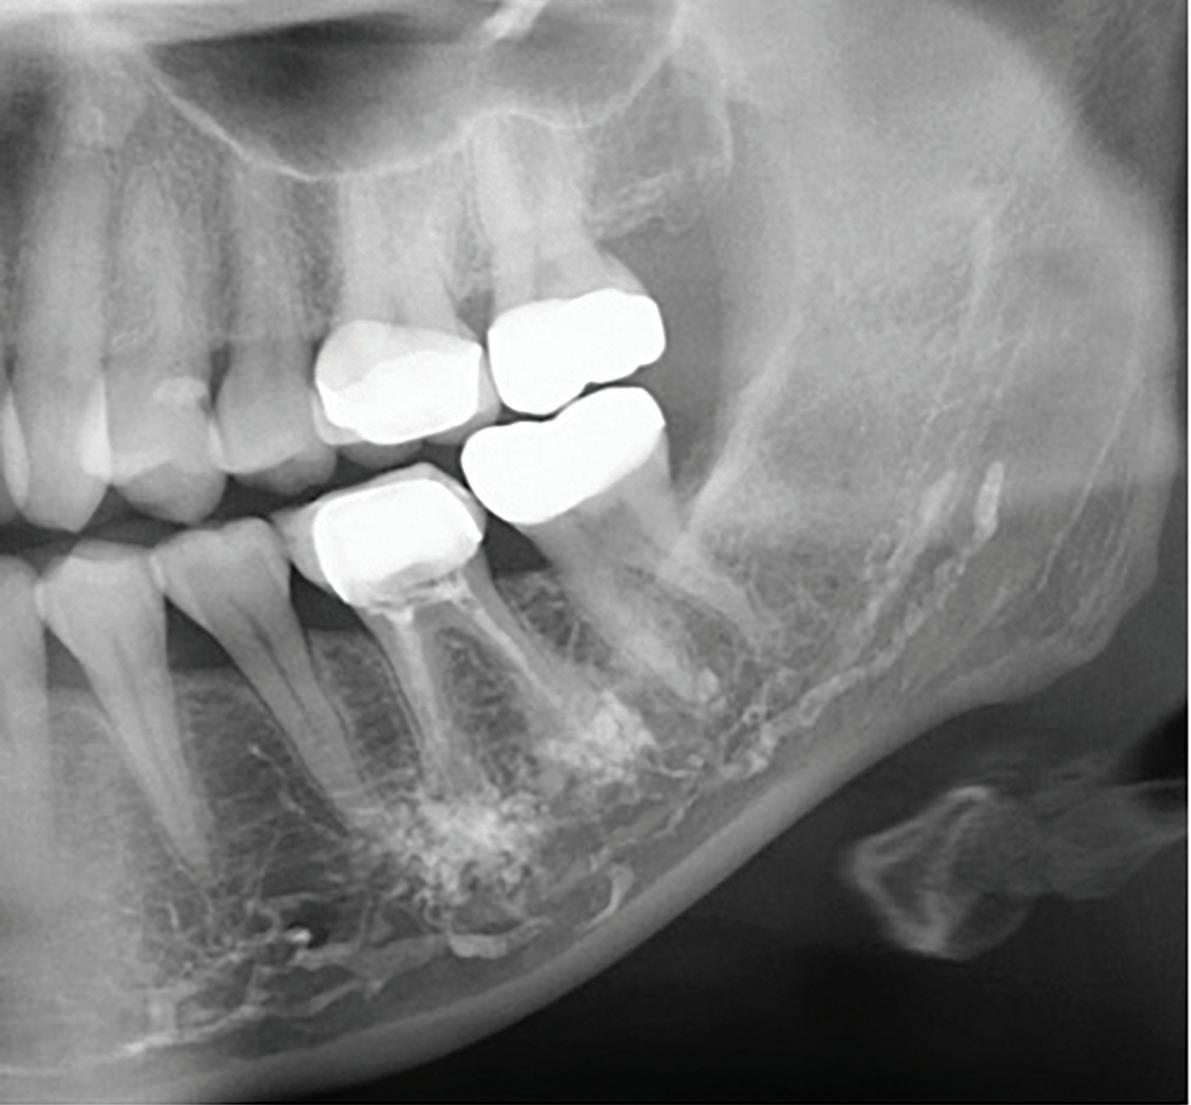

Apical root resorption and external defects: Careful evaluation for root resorption and other external anomalies is essential. Apical root resorption can complicate endodontic treatment by eliminating the natural apical constriction, a key anatomical barrier against extrusion. Resorbed apices are also prone to overinstrumentation, as they lack resistance to file advancement. An underrecognized anatomical risk factor closely associated with apical resorption is fenestration, a defect in the cortical plate where a portion of the root protrudes through the bone. Irrigants or materials extruded from teeth with fenestrations may enter directly into soft tissue or mucosal spaces, dramatically increasing the risk of postoperative swelling, pain, and delayed healing (Figure).(3)